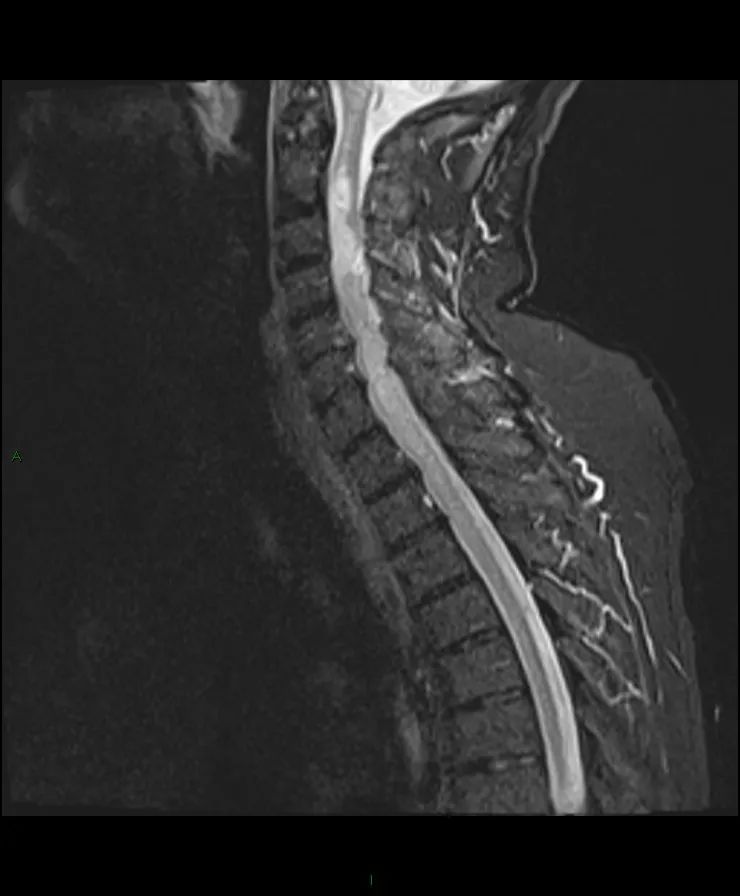

【病例】脊髓星形细胞瘤1例MR影像-1

颈脊髓在C2和T1之间肿块,T1等信号,T2高信号,不规则的非均匀强化。